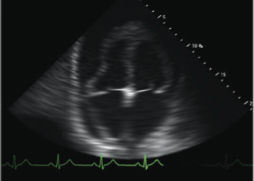

BEDSIDE ECHOGRAPHY MODULE:

The Bedside Echocardiography Module incorporates 10 hands-on tasks and clinical cases, accompanied by comprehensive didactics.

The simulation environment combines high level of realism with advanced educational aids, featuring:

- Step by step dedicated Bedside Echocardiography tasks promoting self learning of the complete protocol as well as anatomy structures recognition.

- Featuring basic standard views complemented by more challenging views such as suprasternal, IVC, apical 2 chambers, apical 3 chambers and more.

- Diverse virtual patient cases taking after real patients, ranging from normal, through slightly abnormal to distinct pathologies.

- Incorporated ECG, Cine loops recordings, calliper measurements and more.

- The clinical cases present scenarios and complaints such as chest pain, mild to severe dyspnea, diverse arrhythmia, diaphoresis, weakness and more.

- With findings such as: normal heart, mitral regurgitation, aortic dissection, pericardial effusion, pulmonary embolism (PE), dilated cardiomyopathy (DCM), Myocardial infarction (MI), tamponade and more.